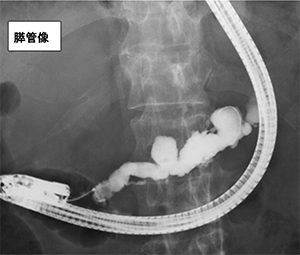

口から十二指腸まで内視鏡を挿入し、胆管・膵管の出口である十二指腸乳頭から、胆管・膵管の中に細い管(カテーテル)を入れます。カテーテルから造影剤を注入し、膵管や胆管のX 線写真をとることで、腫瘍や結石、狭窄などを評価することが出来ます。同時に胆汁や膵液といった消化液を採取したり、病変部から組織や細胞を取って検査することで、癌などの診断も可能です。

胆管を造影したX線写真

膵管を造影したX線写真